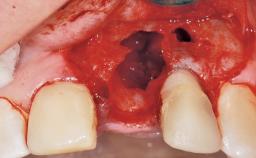

Late Flapless Placement of an Implant in a Maxillary Left Central Incisor Site

A 39-year-old male patient presented with a chief complaint of discomfort and gingival discoloration around his maxillary left central incisor. He was in good general health and was a non-smoker. His past dental history was significant because of the traumatic fracture of tooth 21 in a sporting accident at age 13. Initial dental treatment included endodontic therapy and a full-coverage restoration. The patient became symptomatic 5 years later, when structural failure of the tooth resulted in the dislodgment of the crown. Endodontic retreatment, apical surgery, and post-and-core restoration were performed.

Soft Tissue Anatomy Intact Defective

Bone Volume Horizontally and vertically sufficient Horizontally deficient Deficient vertically or deficient vertically AND horizontally

Bone Volume Deficient horizontally, requiring prior grafting